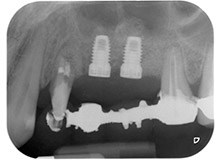

Фиг. 1: 58-годишна пациентка. Предоперативната рентгенография показва апикално-периодонтална лезия на зъб 24 и хоризонтална загуба на алвеоларна кост във втори квадрант.

58-годишна пациентка се оплаква от болка и повишена подвижност в нейния мост върху зъб 24 с функция на абатмънт. На лице е периодонтално възпаление с дълбочина на джоба 7 mm мезиобукално и повече от 12 mm дистално, както и включена 3 градусова фуркация. Освен това, рентгенографията показва обширна периодонтална лезия около апикалната зона на (друго място) предварително ендодонтски обработен зъб 24 (Фиг. 1).

В букалния корен, цялата вестибуларна и дистална кост липсва. Захващането е значително ограничено до палатиналния корен, подчертавайки предварително лошата прогноза. Зъб 27 също откри намалено хоризонтално захващане и минимално апикално разреждане (Фиг. 1) без клинични симптоми.